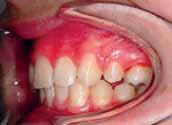

The patient had moderate Class II skeletal pattern with average Frankfort-mandibular planes angle and lower anterior face height. There was no facial asymmetry and the lips were incompetent with the lower lip trapped at rest behind the upper central incisors (Figure 1).

and causing trauma to the palatal mucosa. The centrelines were coincident and the buccal segment relationship was 1/2 unit Class II on both sides (Figure 2).